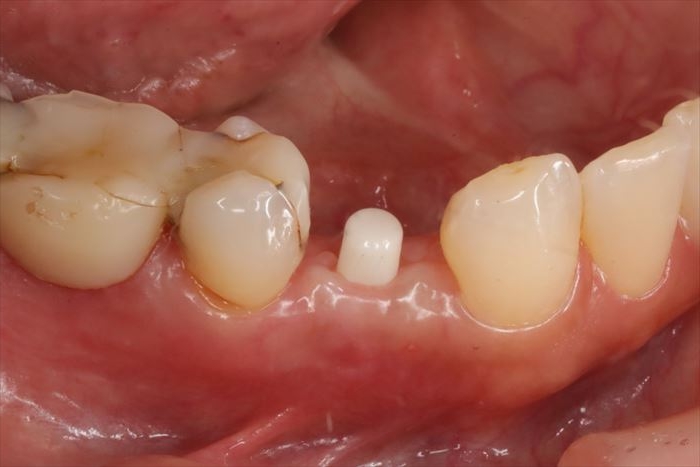

インプラント埋入から6週後の状態です。(2025.10.24)

_

CO2レーザーで歯肉を蒸散してインプラントのマージンを露出させます。